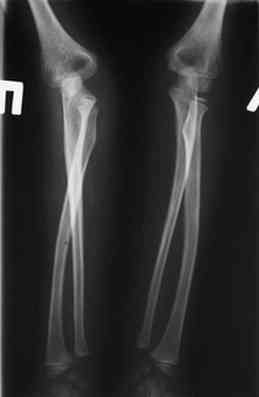

оперировали подобный случай около 6 мес назад. Отличие только в одном- давность травмы была до 2х лет. Использовали методику описанную в "Pediatric fractures and dislocations" Lutz von Laer, M.D.

Артротомия, иссечение рубцов, остатков кольцевидной связки. На проксимальный отдел локтевой кости стержневой аппарат (рекомендуют

Compact II выпущеный Stryker Howmedica, но за неименеем...), остеотомия проксимального отдела локтевой кости, вправление головки лучевой кости, замыкание аппарата, проверка стабильности головки

лучевой кости в движении, ушивание без пластики кольцевидной связки.